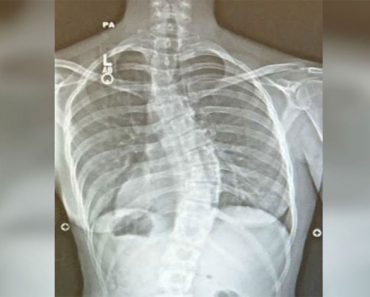

No podían explicar sus terribles dolores de cabeza. Entonces vieron esto por rayos-X…